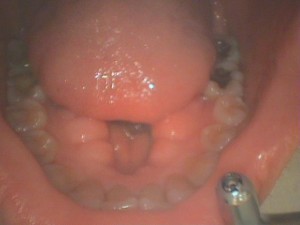

写真は下顎の骨隆起です。

どちらのケースもかなり大きく舌の入るスペースを侵害しています。